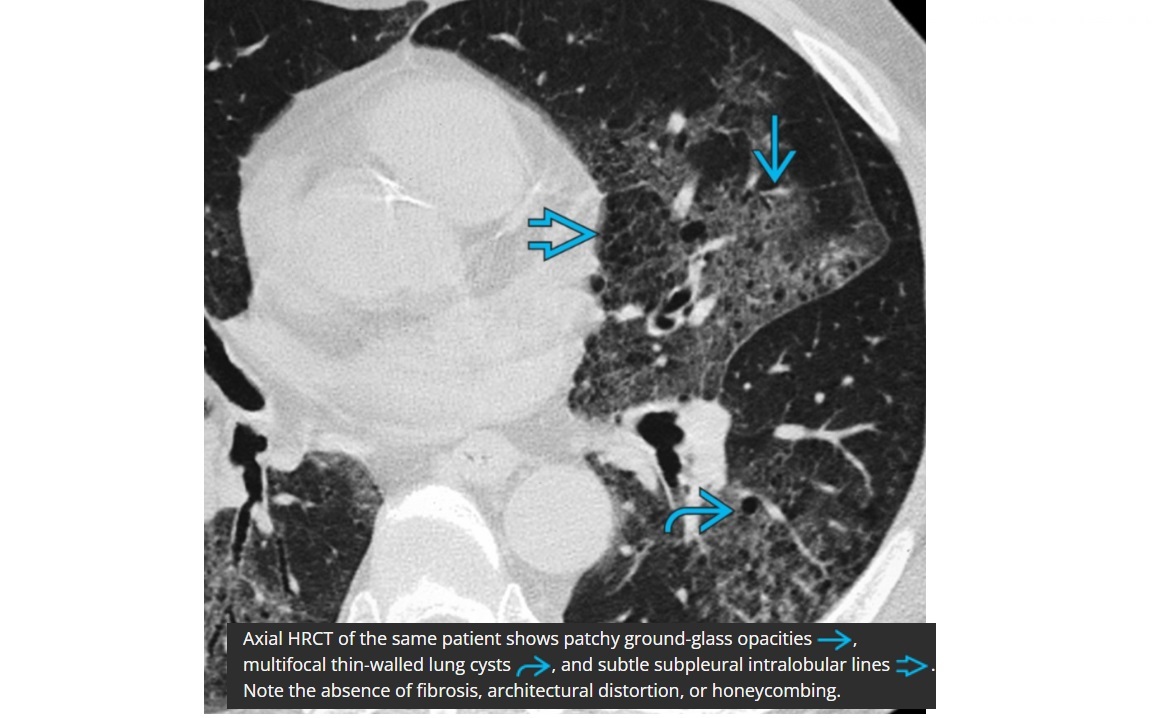

DIP

Bilateral, lower zone predominant ground-glass opacities

± subpleural **intralobular lines/retiuclations **

Small, round,** thin-walled** (2-4 mm in diameter)

Spectrum/similar HRCT to RB-ILD